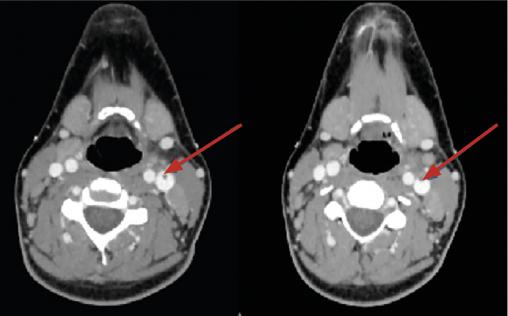

Le scanner cervico-thoracique (fig. 1 et 2 ) montre une thrombose de la veine jugulaire interne gauche ainsi qu’un épanchement pleural bilatéral et une pneumopathie des deux côtés sur emboles septiques, permettant de poser le diagnostic de syndrome de Lemierre.

L’aspect radiologique typique est celui de notre observation. Les abcès pulmonaires, multiples et disséminés par voie hématogène, sont évocateurs. Ils font rechercher une thrombose jugulaire ou de ses collatérales.